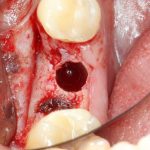

Рекомендации по установке имплантов. Для всех. Часть V.